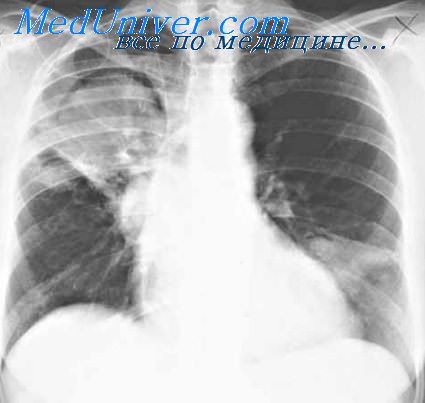

Крупозная пневмония

- Крупозная – данную разновидность также называют долевой. Это обусловлено тем, что недуг поражает определенные доли легкого. Чаще всего встречается у взрослых пациентов.

Крупозную пневмонию вызывают пневмококки. Данная разновидность воспаления легких довольно распространена. Недуг поражает всю поверхность легкого или только его треть. Чем больше площадь поражения, тем выше риск возникновения последствий. При выявлении тотальной пневмонии больного экстренно госпитализируют. Это объясняется плохим прогнозом. В клинической картине присутствует: